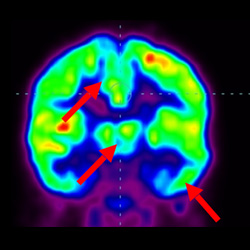

干細(xì)胞治療腦癱后改善的客觀放射學(xué)證據(jù)

細(xì)胞治療前 PET CT 掃描顯示神經(jīng)組織中的藍(lán)/黑色區(qū)域,表明腦癱引起的大腦損傷。